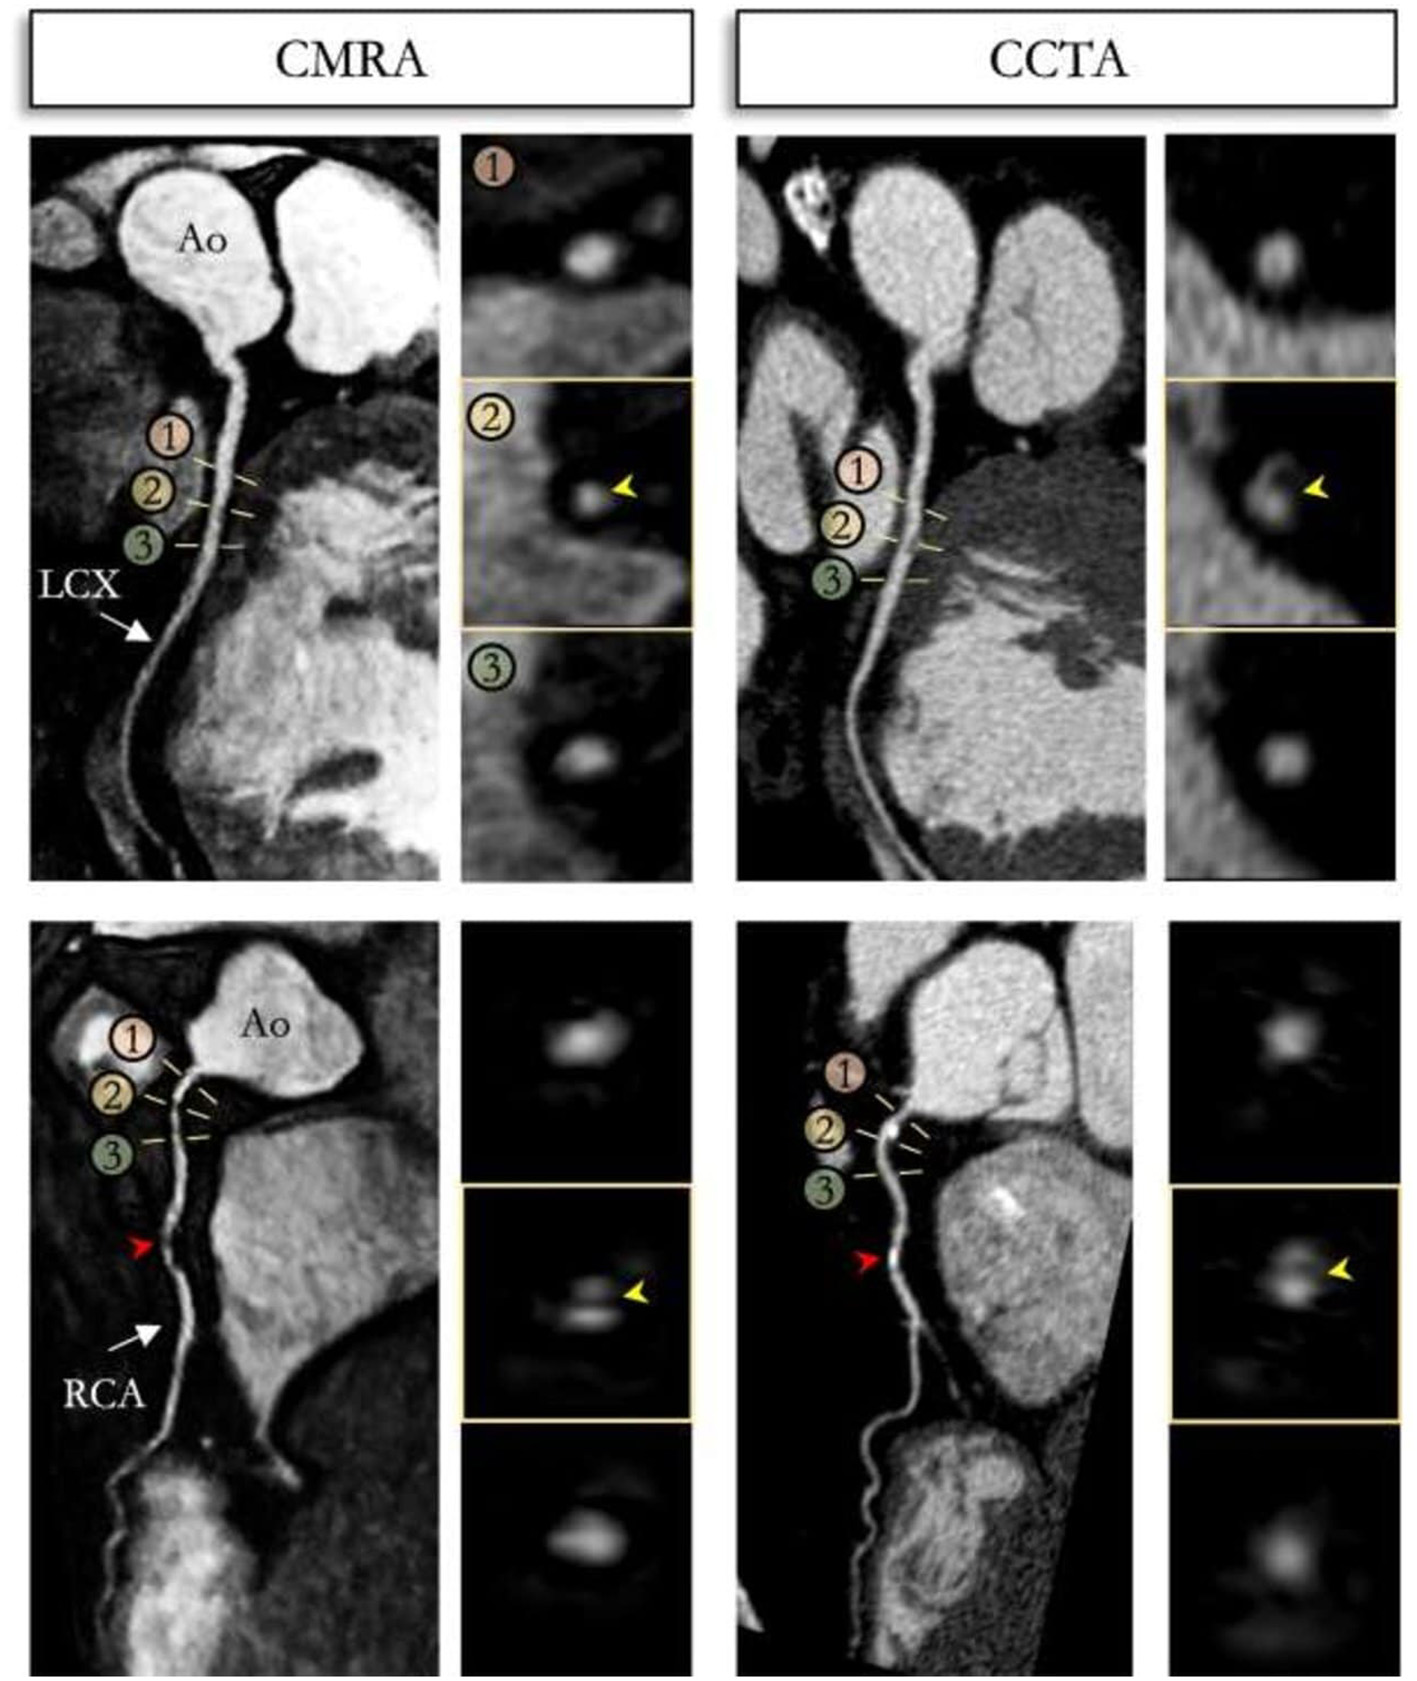

An alternative approach is a golden-step Cartesian trajectory with spiral profile ordering k-space acquisition, which can be combined with iNAVs to enable respiratory binning as described above (61). Using the binned data, it is possible to estimate and subsequently reconstruct the 3D non-rigid respiratory motion by combining beat-to-beat 2D translational and bin-to-bin 3D non-rigid motion correction to a common reference position (Figure 7) (62). This approach can increase the signal to noise ratio compared with radial sampling, whilst also improving image quality compared with 2D rigid translational motion correction frameworks. To shorten acquisition times and therefore enable higher spatial resolutions, Bustin et al. (63) adapted a highly undersampled patch-based CMR reconstruction framework (64) to propose a 3D patch-based low-rank (PROST) reconstruction, enabling <1 mm3 spatial-resolution free-breathing whole-heart 3D CMRA with <10 min predictable acquisition time with 100% scan efficiency. In a validation cohort of healthy subjects, image quality was comparable to the fully sampled acquisition and significantly improved compared to both iterative SENSE and compressed sensing reconstruction methods. This framework has been extended to include bin-to-bin non-rigid respiratory motion correction and has been compared against CCTA in patients with suspected CAD (Figures 8, 9) (65). In a single centre study of 50 patients, this CMRA technique obtained diagnostic image quality in 95, 97, 97, and 90% of all, proximal, middle and distal coronary segments, respectively. Furthermore, 100, 97, 96, and 87% of left main stem, right coronary artery, left anterior descending and left circumflex artery segments, respectively on CMRA were of diagnostic image quality (Figure 10) (66). The sensitivity, specificity, positive predictive value, negative predictive value and diagnostic accuracy were as follows: per patient (100, 74, 55, 100, and 80%), per vessel (81, 88, 46, 97, and 88%) and per segment (76, 95, 44, 99, and 94%), respectively, with an average acquisition time of 10.7 min at 0.9 mm isotropic spatial resolution (66).

Figure 9

Reformatted non-contrast whole-heart sub-millimeter isotropic CMRA (left) and CCTA (right) images along the LCX (top) and RCA (bottom) are shown for a 54 year-old male patient. The CMRA dataset was acquired in 9 min with 100% scan efficiency (heart rate of 57 bpm). The CCTA images demonstrate mild (25–49%) disease with a calcified plaque within the proximal RCA and severe disease (70–90%) with a partially calcified plaque in the mid-segment of RCA (red arrows), and minimal (0–24%) disease with calcified plaque in the mid-segment of the LCX. Luminal narrowing is seen on the cross-sectional views at the sites of coronary plaque on the CMRA images (yellow arrows). LAD, left anterior descending artery; RCA, right coronary artery; LCX, left circumflex artery; Ao, aorta. Adapted with permission from Bustin et al. (65).